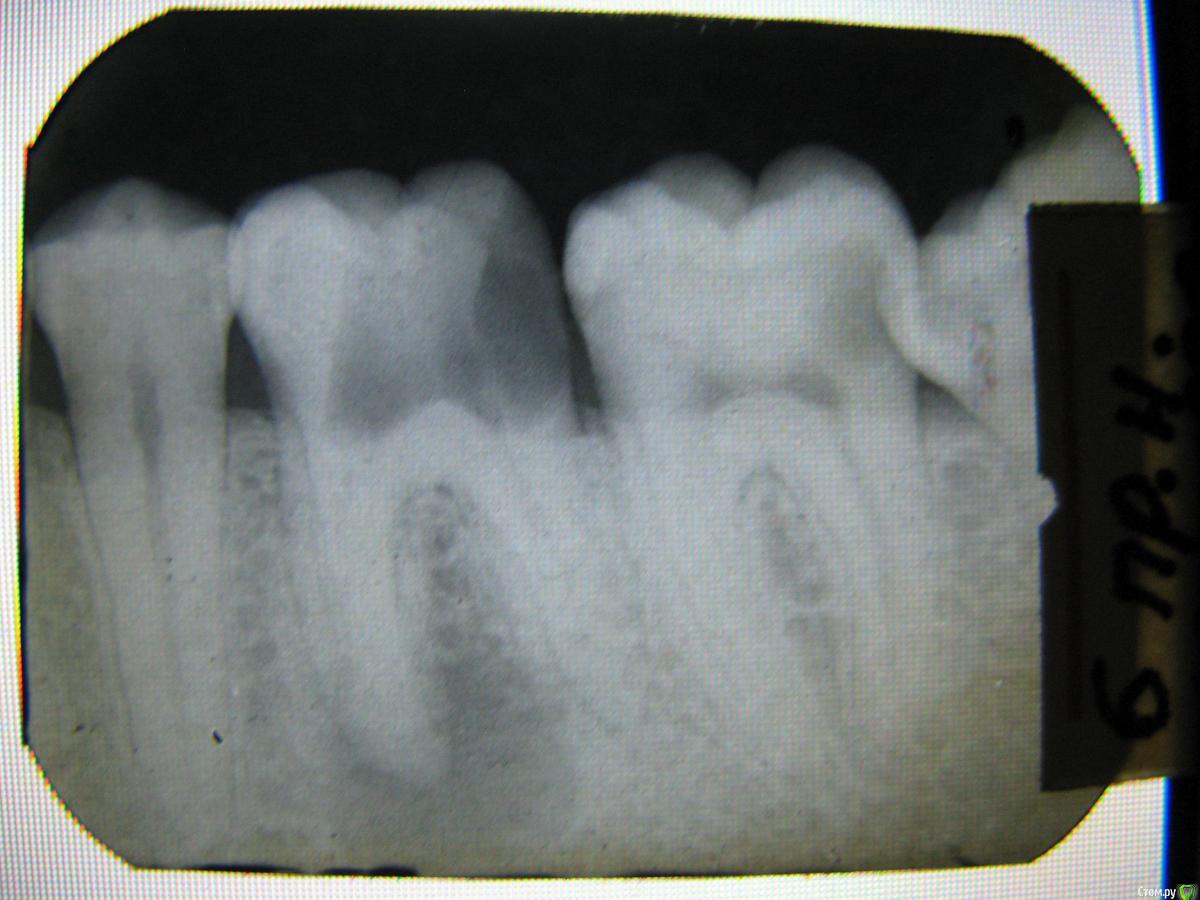

~~SERG~~ Опубликовано 26 декабря, 2016 Поделиться Опубликовано 26 декабря, 2016 Добрый день!Вопросы по 46 47, в первую очередь по 46. История 46 зуба началась в 1999 году, когда мне предложили в коммерческой клинике заменить "советсткую" химическую пломбу на новую, светоотверждаемую. заменили. через два дня флюс и депульпирование зуба.снимок "46_1999.jpg" это состояние после вскрытия новой пломбы и каналов, видно разряжение костной ткани в районе корня со стороны 45. Ссылка на комментарий